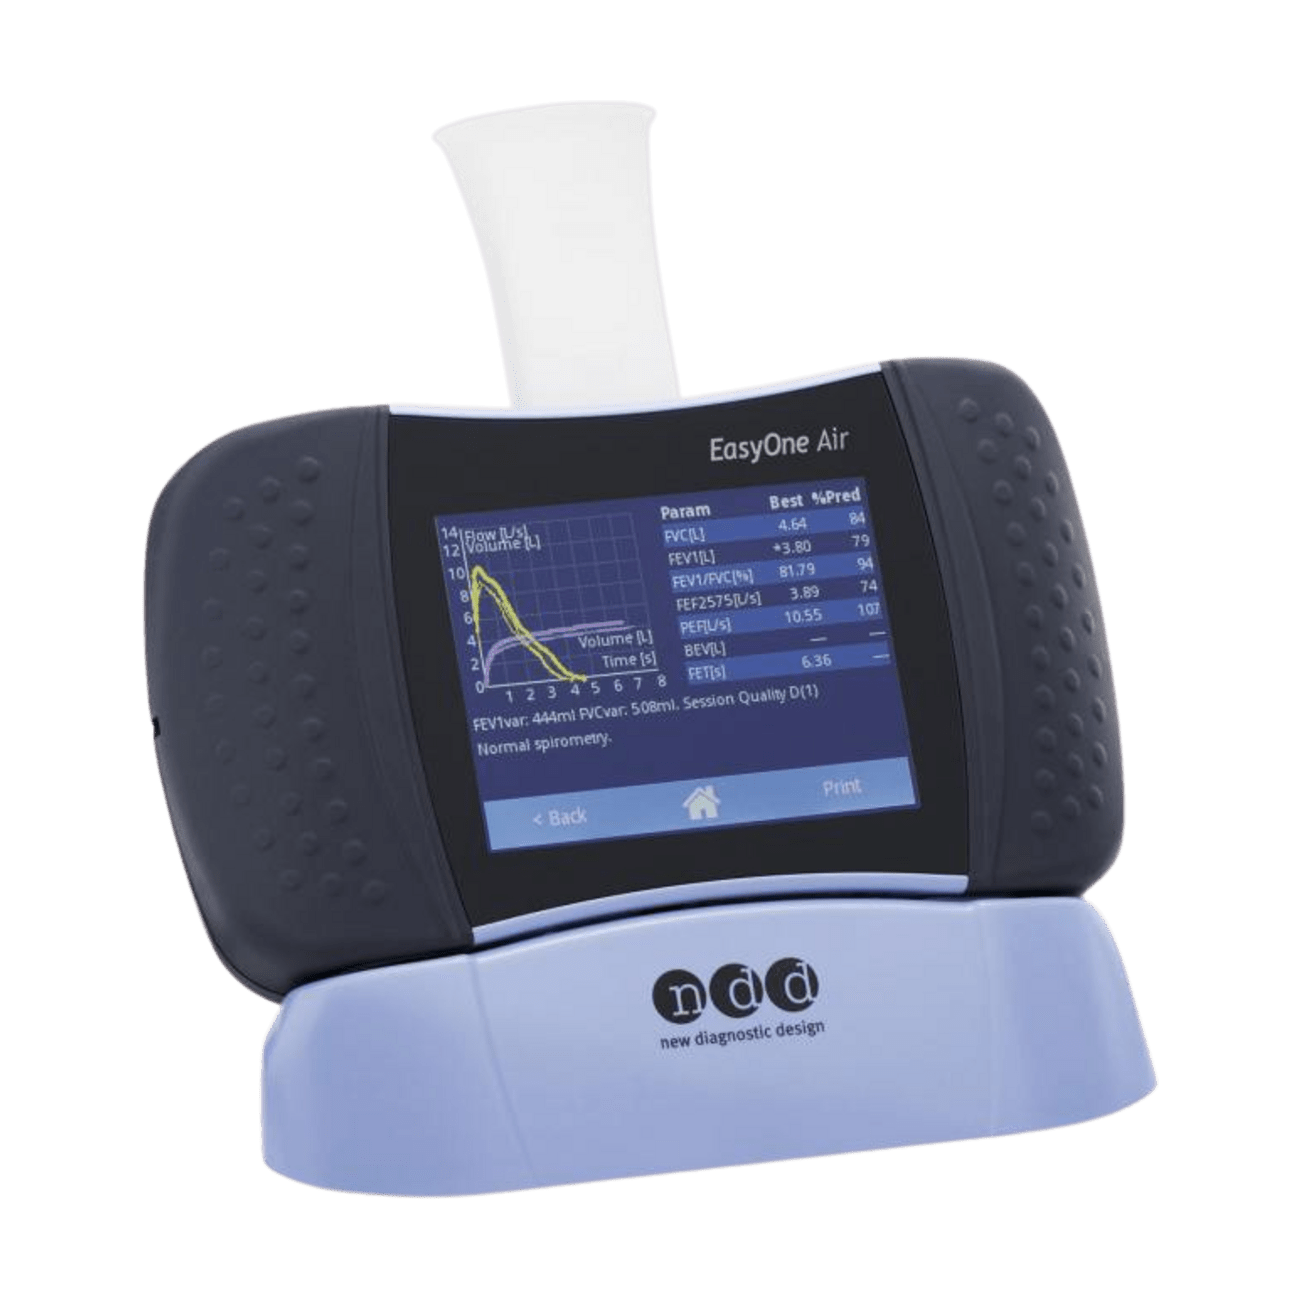

EasyOne® Air

- Großer Farb-Touchscreen

- für bequeme Dateneingabe und farbige Kurven- und Datendarstellung

- Intuitive Benutzerführung

- Vollständig kalibrationsfreies Gerät

- TrueFlow™ gewährleistet genaue Durchfluss- und Volumenmessungen über die gesamte Lebensdauer der Geräte.

- Ultraschall Strömungsmesstechnologie

- Hohe Messgenauigkeit (2% bei VC)